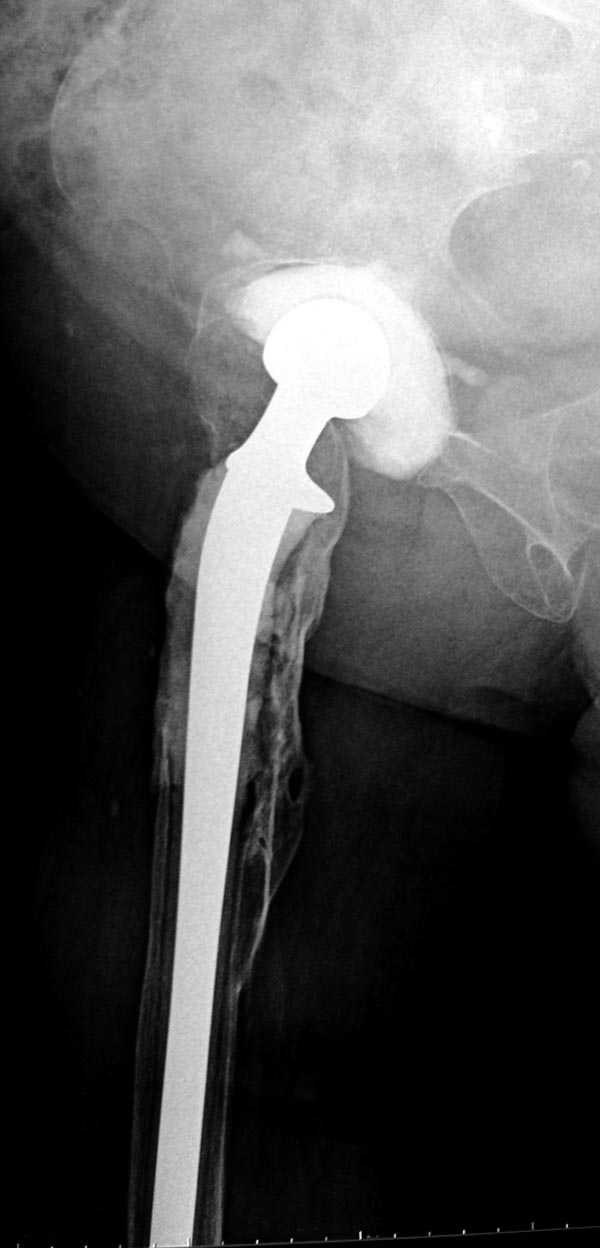

Вот снимки по свежей ситуации, парень 19 лет, длинный оскольчатый перелом бедра от шейки до в-с/3. давно уже ходит на своих ногах.

Представленные Вами рентгенограммы действительно являются примером качественной фиксации спице-стержневым аппаратом. Они, как ни что другое, многое иллюстрируют.

Кроме того, было бы ошибкой ставить знак равенства между нашим и Вашим пациентами. Они не только не похожи, разница между ними просто огромная. Говорю это не для того, чтобы задеть Вас или обидеть. Ни в коем случае. Просто теперь я понимаю, что Ваше мнением строится на простом преломлении Ваших подходов к лечению пациентов со свежими переломами, на ситуацию, абсолютно несопоставимую, подобную нашей.

Готов поспорить, не так уж огромна разница. Я вполне понимаю, что фиксация свежего отломка у 19-летнего парня и чего там осталось от головки-шейки-вертелов у вашего немолодого пациента - это не одно и то же. Но я продолжаю настаивать на том, что вы далеко не исчерпали возможности данного метода. А то, что вся ситуация происходит на фоне гнойной раны чуть ли не в самом очаге - вообще для меня делает непонятой дискуссию о выборе метода, метод выбора уже применяется, и даже успешно.

Компоновку данного аппарата, в котором дистальный отломок фиксирован лишь на дистальном уровне, а проксимальный вообще сам по себе никак, только через бывший сустав, назвать стабильной никак нельзя. Нет стабильности - нет нормального заживления, но есть осложнения, надеюсь, это-то можно экстраполировать на вашего больного?